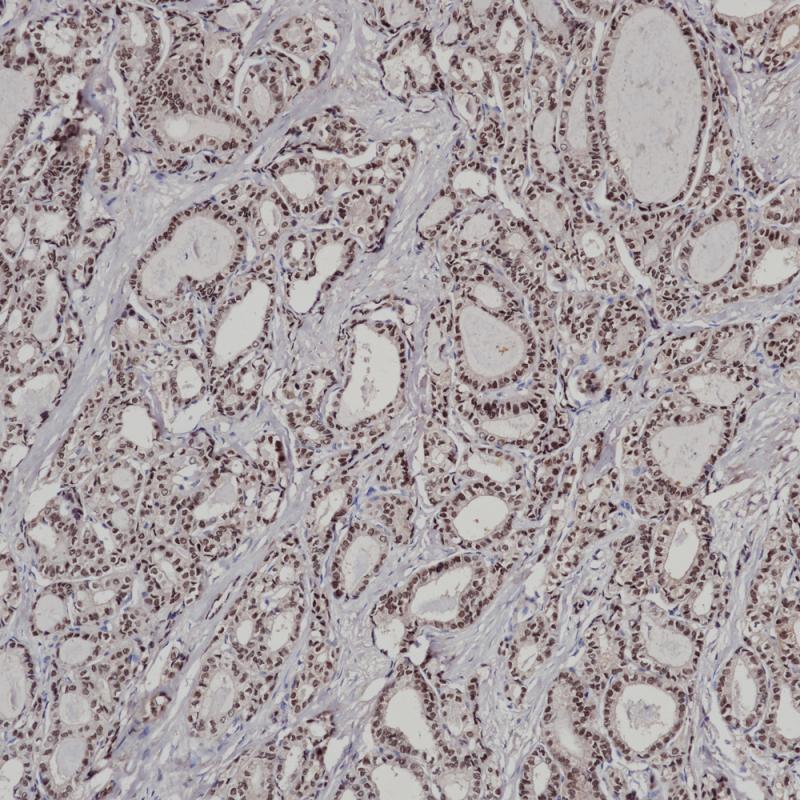

MHC II(DRα chain) 重组兔单克隆抗体

主要组织相容性复合体 II 类(MHC II 类)分子是在巨噬细胞、树突细胞和 B 细胞等抗原呈递细胞表面表达的异二聚体的跨膜糖蛋白。在人体中,MHC II 类蛋白复合体被人白细胞抗原基因复合体 (HLA) 编码。MHC II可在 B 淋巴细胞、活化的 T 淋巴细胞、活化的自然杀伤 (NK) 细胞等表达。

阳性对照

食管